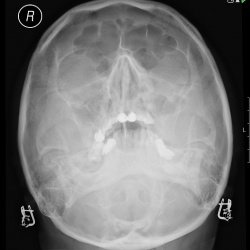

Пациентка 1939 г рЖалобы на периодические выделения из лев уха, головные боли, головокружение, снижение слуха ))В анамнезе левосторонний хронический средний отит, мезотимпанит с периодич обострением...